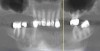

The Toronto Conference in 1982, chaired by Professor George Zarb and presented by Professor Per-Ingvar Brånemark, was a seminal event that changed edentulous treatment planning concepts irrevocably. No longer was it necessary to rebuild lost bone through grafting alone in either arch. The severely atrophic mandible, for example, could be treated with as few as four implants used to support a bone-sparing prosthesis through integrated tooth analogs, as demonstrated in Figure 1 through Figure 3. Here, an 81-year-old patient presented with severe mandibular atrophy (Figure 1) from denture wear since a very young age and had a history of being unable to manage a mandibular prosthesis despite numerous attempts at new denture construction. Four vertical machined-surface osseointegrated implants were placed in 1983 by Professor Brånemark, and all four penetrated the inferior cortex up to 3 mm to 4 mm in depth, as shown on the immediate postoperative panoramic film (Figure 2). At 4 years and 5 months, reparative bone had formed to the apices of all implants (Figure 3), and all of them remained in uncompromised function until the patient passed away at age 90.

Fig 1. 81-year-old patient had severe mandibular atrophy from many years of denture wear and had a history of inability to manage a mandibular prosthesis.

Figure 1